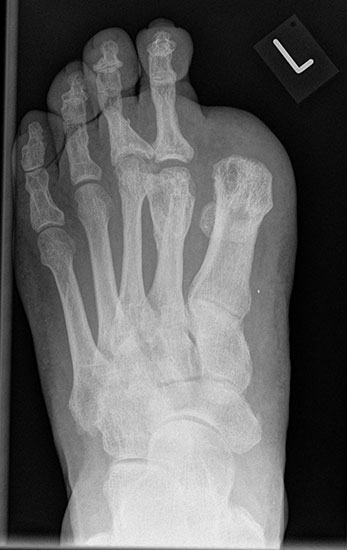

Die bewährten Amputationslinien am 1. Strahl finden sich in Abb. 3.

Tennisschlägerartige Umschneidung der Großzehe (Abb. 11). Das Metatarsale wird so osteotomiert, dass an der Medial- und Plantarseite keine Knochenkanten verbleiben (Abb. 12).